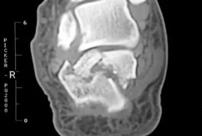

跟骨骨折冠状面影像